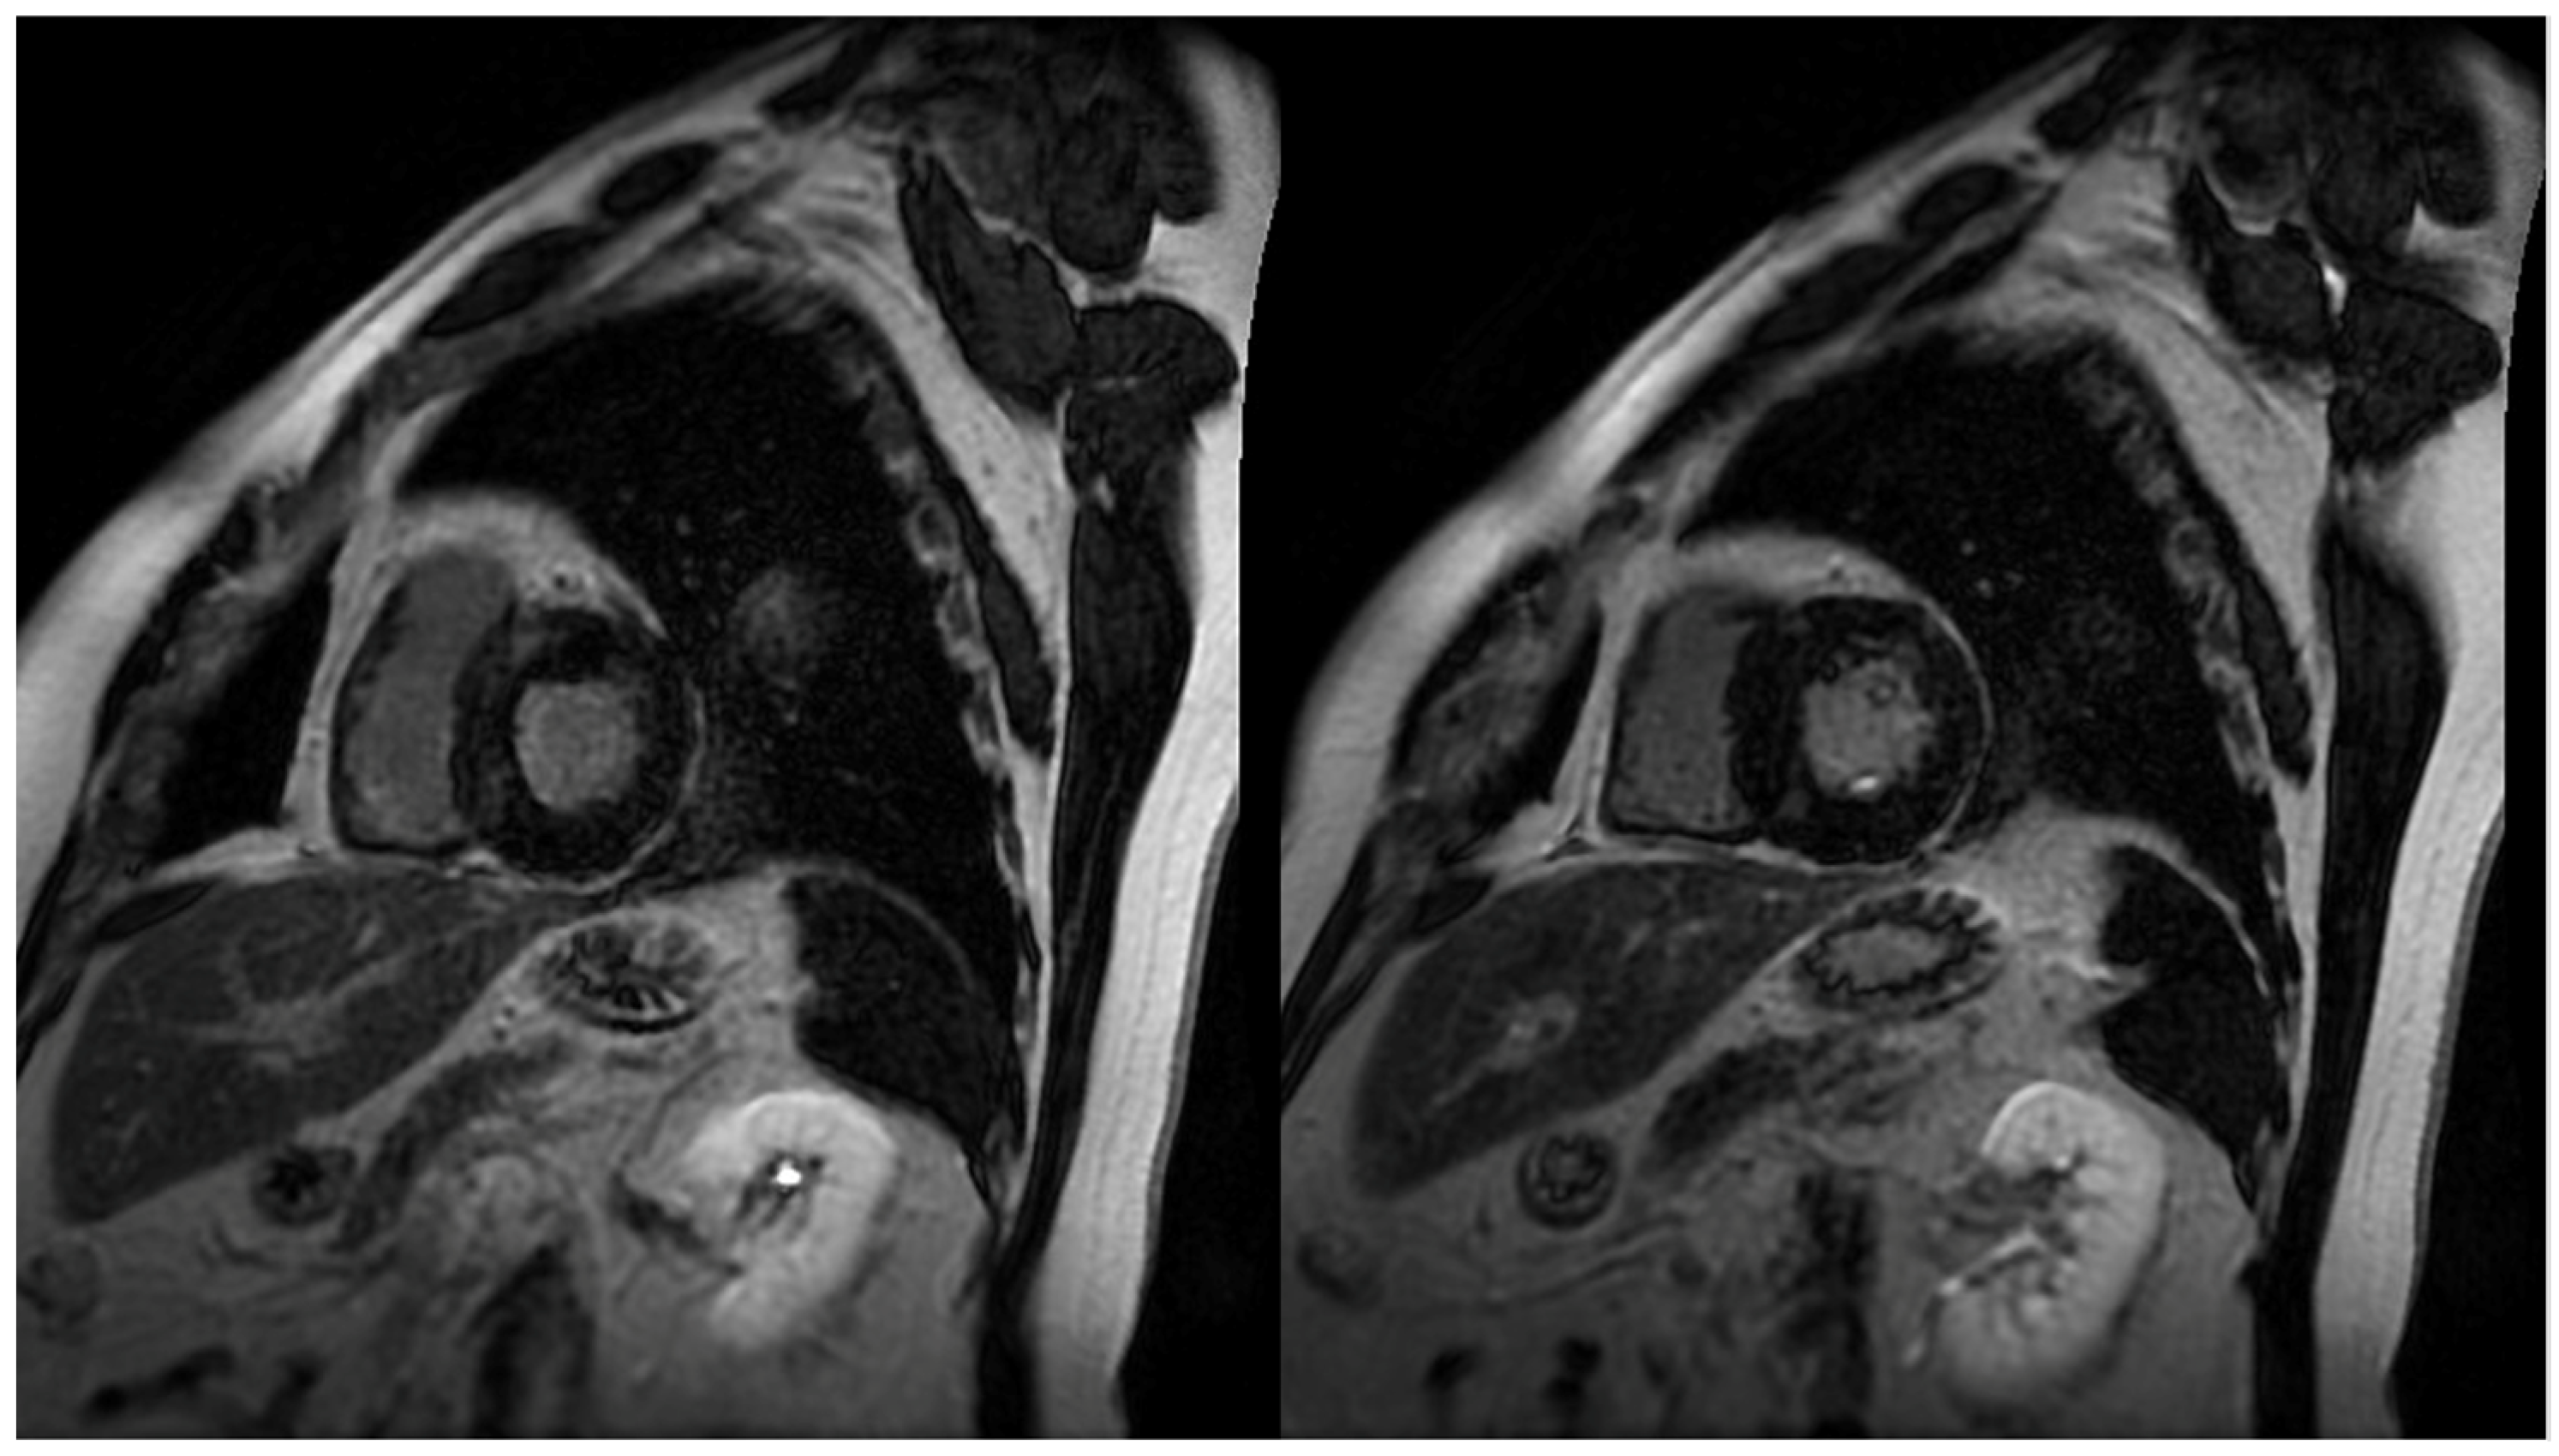

Figure 1.

Short axis images demonstrating patchy late gadolinium enhancement (LGE) in hypertrophic cardiomyopathy (HCM) patients. Common patterns identified in HCM patients include localization in segments with greatest left ventricular hypertrophy (LVH), and right ventricular (RV) insertion points.

The identification and quantification of LGE is a valuable feature of CMR, changing the paradigm in how ischemic and non-ischemic myocardial diseases are assessed (Figure 1). It represents myocardial fibrosis and is a predictor of both a higher mortality rate and the progression towards heart failure amongst HCM patients [19]. The mean reported prevalence of LGE is 65%, but may be present in up to 86% of HCM patients [7,20]. Typical patterns include localization to the mid-wall, located in segments with the greatest LVH, and at RV insertion points. Thus, peculiar patterns of LGE, during the assessment of LVH, can be attributed to other diagnoses that may include, but are not limited to, Anderson–Fabry disease or cardiac amyloidosis (CA). The distinction between the location of LGE includes the type of fibrosis, whereby intramural mid-wall LGE is considered a marker for replacement fibrosis, whilst LGE at RV insertion points suggests interstitial fibrosis [21]. Replacement fibrosis increases diastolic dysfunction and ventricular stiffness [10], and plays a role in the progression of heart failure. It is well acknowledged that the presence and extent of LGE is associated with disease severity, which includes the extent of LV thickness, remodeling, and dysfunction [17,22]. It has also been suggested that it may act as a substrate for both arrhythmias and heart failure [23]. More importantly, LGE is an independent predictor of sudden death, whereby if >15% occupies the LV wall, it results in adverse remodeling and a twofold increase in the risk of sudden death [24]. The presence of LGE is thus proposed to be a substrate, accounting for a greater risk, in ventricular tachyarrhythmias [23,25].

LGE patterns in HCM patients do vary greatly, with a wide range of locations and distributions being described. The most common pattern, affecting 30% of patients, is described as patchy, affecting the septum and free LV wall [26]. Other locations include the isolated involvement of the apex, septum, lateral wall, and the right ventricular insertion points. Often, extensive LGE is located in the walls of apical aneurysms associated with HCM [27]. LGE is, however, frequently absent in HCM patients without LVH, suggesting the association between pathological hypertrophy and LGE enhancement [27]. In addition, the presence of LGE has not shown a clear relationship with a reduction in ejection fraction (EF), but has been implicated in myocardial stiffness, regional wall motion abnormalities, and magnitude of LVOT obstruction [26,28,29]. Nonetheless, it dictates follow up, as those with significant LGE do require closer monitoring given the risk of progression in systolic dysfunction [30,31].